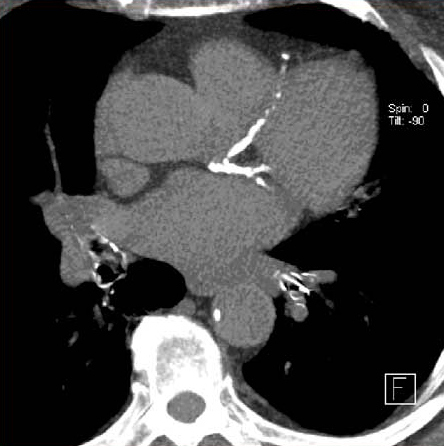

Valor de la ausencia de calcio coronario para descartar obstrucción significativa

Un puntaje de 0 en el calcio coronario medido por angiotomografía computada reduce sustancialmente el riesgo de enfermedad coronaria en los adultos mayores, pero en los pacientes más jóvenes se halló que una proporción considerable de la coronariopatía obstructiva ocurre en aquellos sin calcio coronario. JAMA Cardiology, 27 de octubre de 2021.